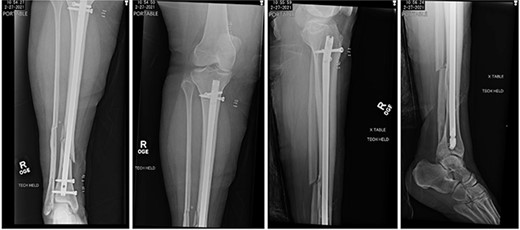

The patient was taken to the operating room on the same day for irrigation and debridement and suprapatellar nailing of the tibia. The cannula and trocar wire were driven in place, and the bone was reamed up to 11.5 mm. A 10 mm diameter Smith and Nephew nail was inserted, and two proximal and two distal interlocking screws were placed. No complications nor injury to the cartilage were noted at the time, and imaging demonstrated appropriate reduction of the fracture (Fig. 2). The patient was discharged home the next day with permission to weight bear as tolerated.

Postoperative radiographs demonstrating reduction of distal tibia/fibula fracture.